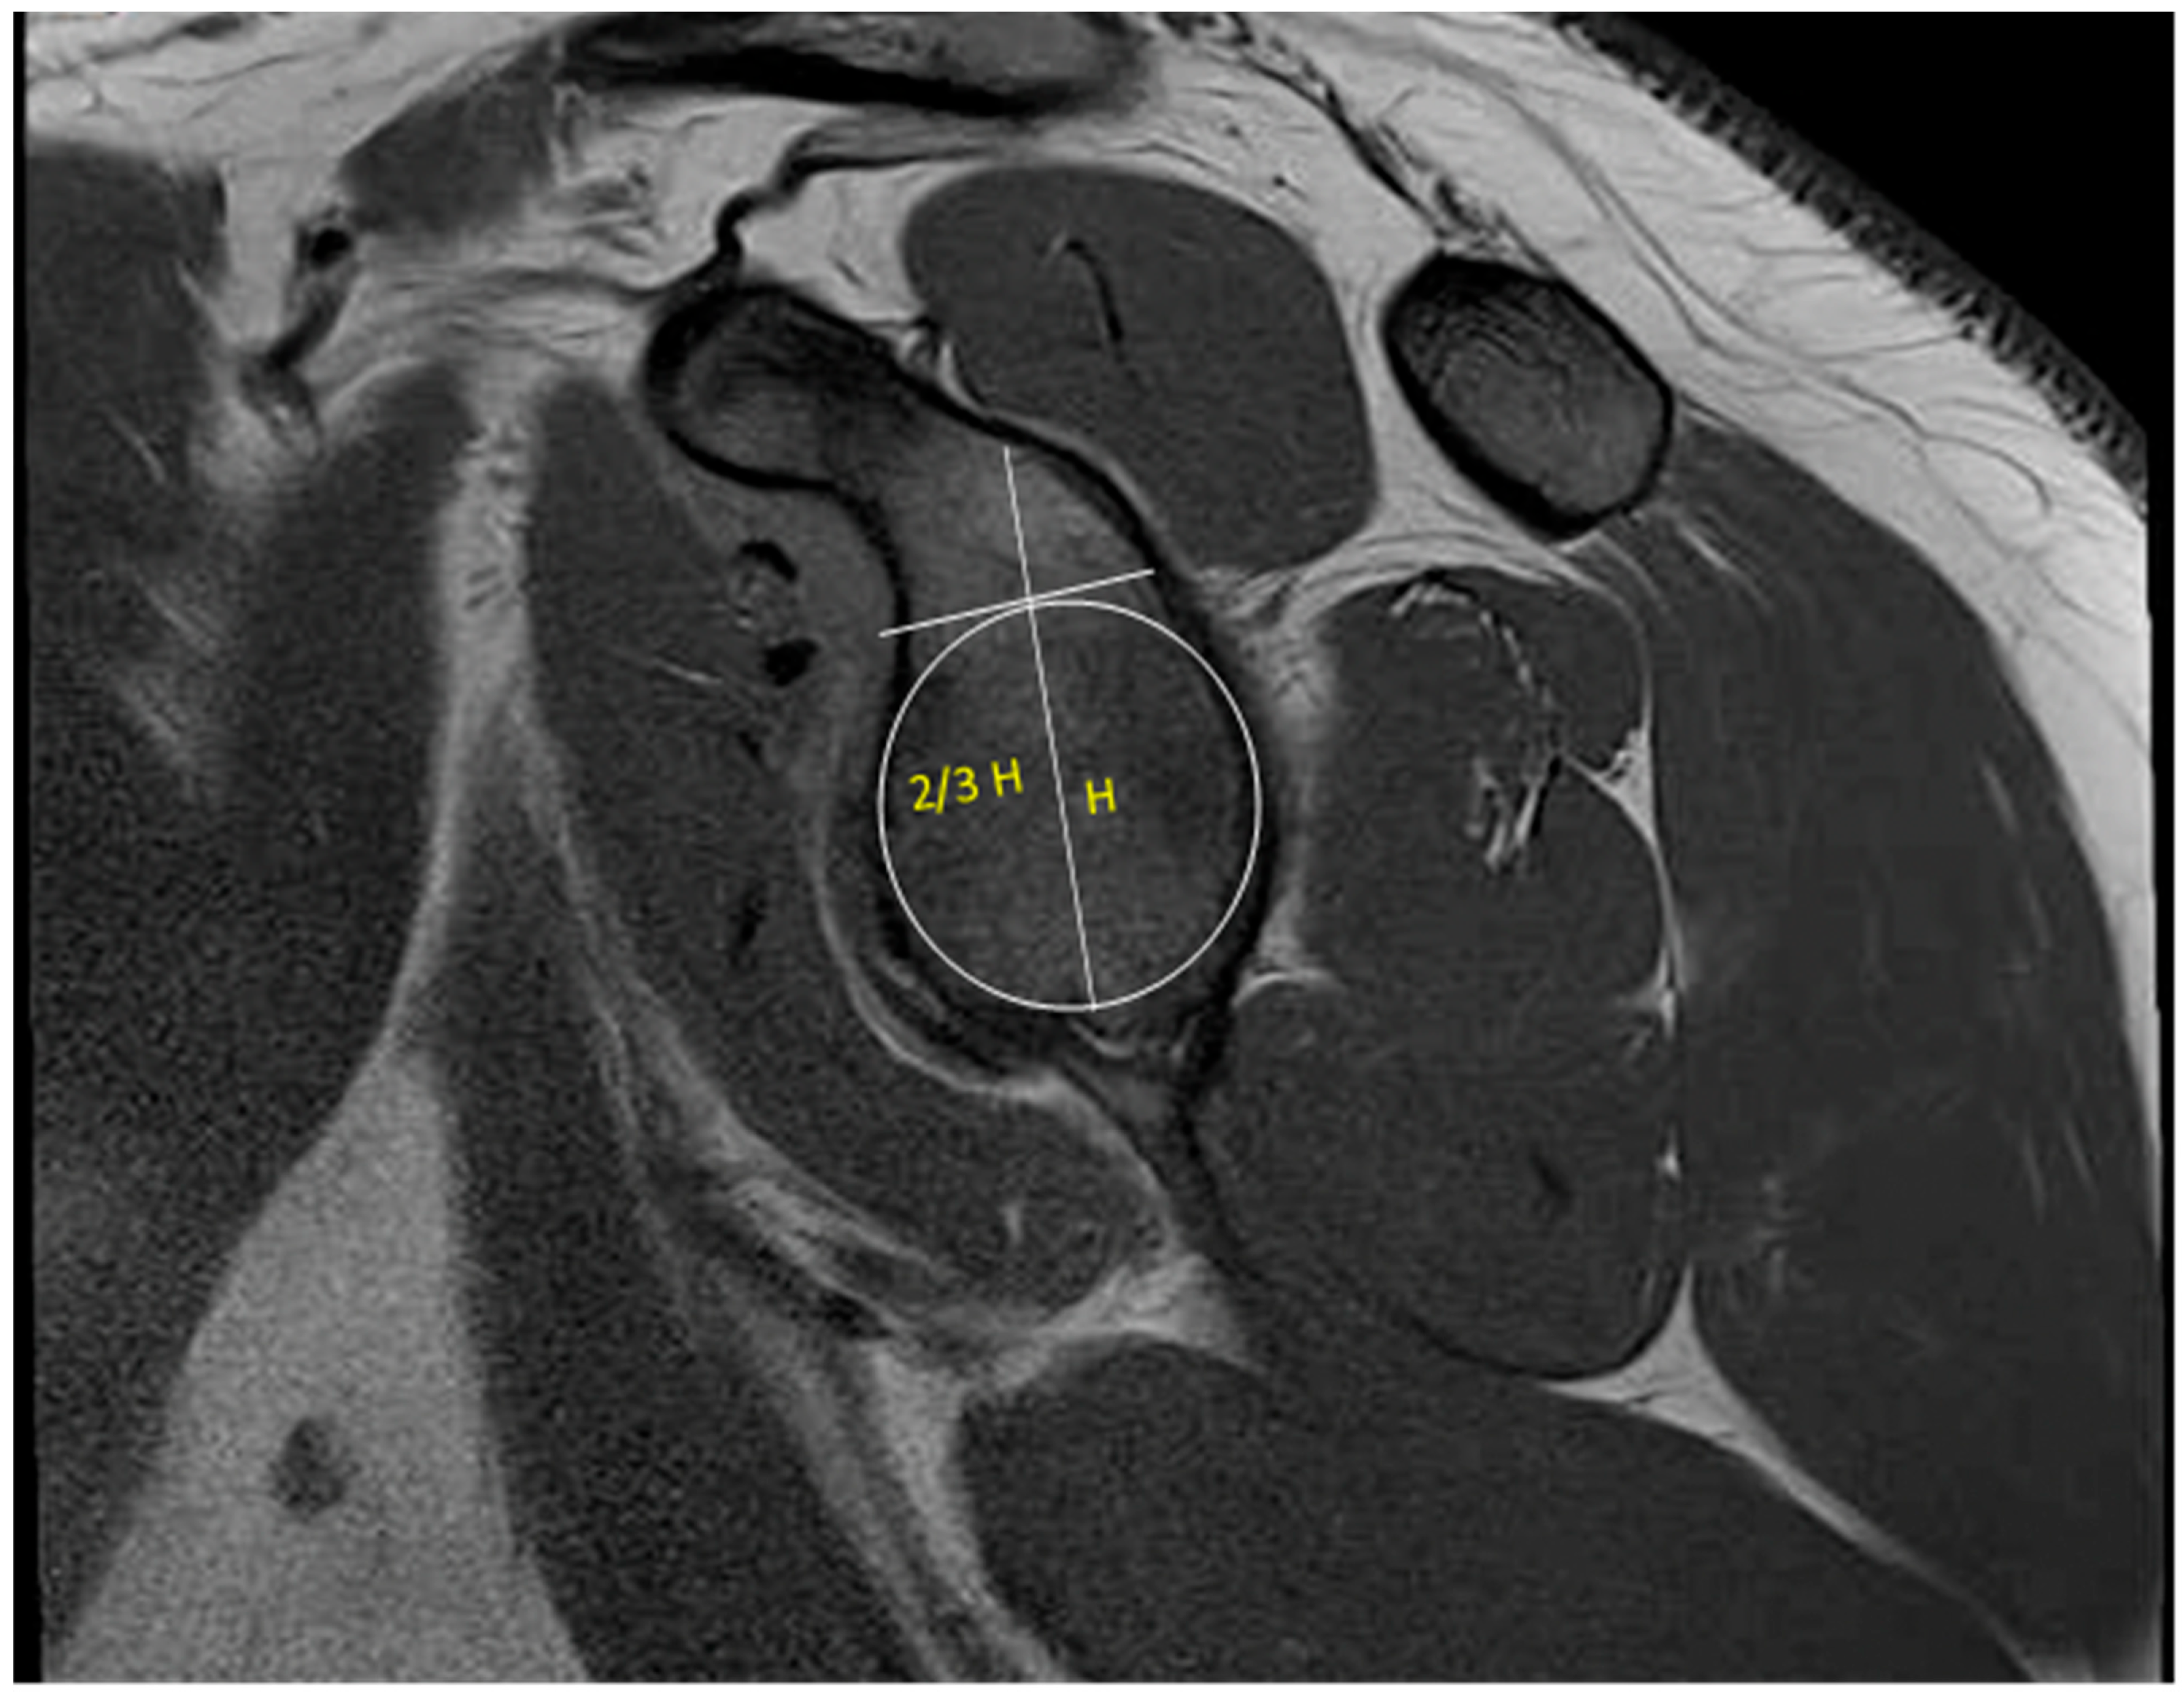

- Makovicka, J.L.; Moore, M.L.; Pollock, J.R.; Rodriguez, M.J.; Shaha, J.S.; Haglin, J.M.; Tokish, J.M. MRI Analysis Demonstrates Improved Reliability in Measuring Shoulder Glenoid Bone Loss Using a Two-Thirds Glenoid Height Technique Compared to the “Best-Fit Circle”. Arthrosc. J. Arthrosc. Relat. Surg. Off. Publ. Arthrosc. Assoc. N. Am. Int. Arthrosc. Assoc. 2023, 40, 666–671. [Google Scholar] [CrossRef]